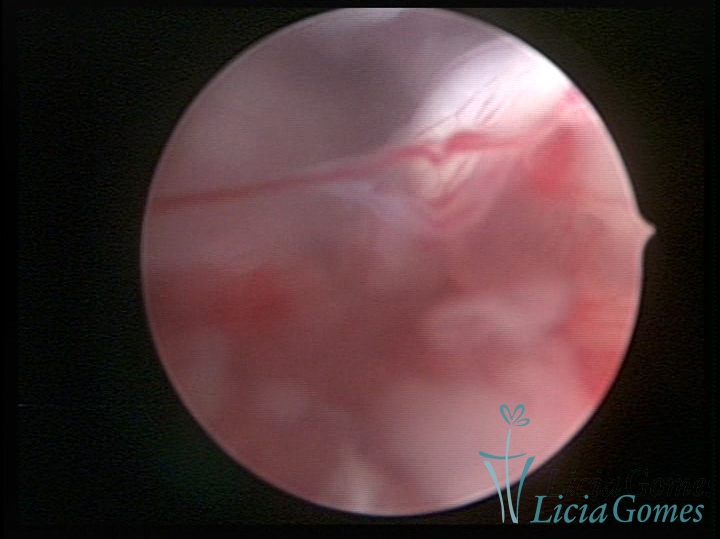

Este pode apresentar uma gama variável de aspectos macroscópicos, com aspecto pseudopolipoide; lembrando tecido cerebroide ou com reação deciduoide;a vascularização superficial é mais evidente e com vasos em formatos de saca-rolha ou espirais visualizando também a vascularização com atípias, com aumento do calibre dos vasos superficiais, pode ser encontrado também tecido em necrose, poderá haver um pequenos dendritos (papilomatoso).